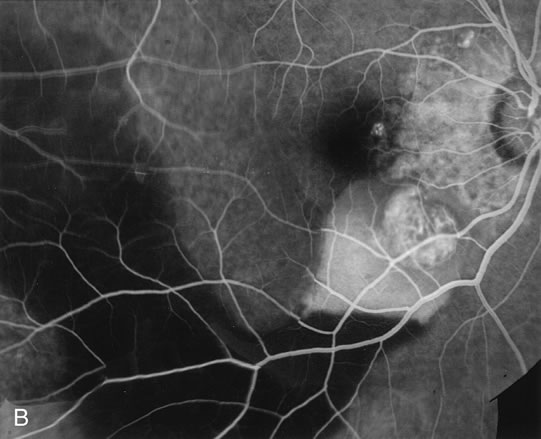

zone in senile macular degeneration. Am J Ophthalmol 93:157, 1982. 8. Yannuzzi LA, Negrão S, Iida T et al: Retinal angiomatous proliferation in age-related macular degeneration. Retina 21:416–434, 2001. 9. Fernandez LH, Freund KB, Yannuzzi LA et al: The nature of focal areas of hyperfluorescence or hot spots imaged with

indocyanine green angiography. Retina 22:557–568, 2002. 10. Ghazi NG. Retinal angiomatous proliferation in age-related macular degeneration. Retina 22:509–511, 2002. 11. Axer-Siegel R, Bourla D, Priel E et al: Angiographic and flow patterns of retinal choroidal anastomoses in age-related

macular degeneration with occult choroidal neovascularization. Ophthalmology 109:1726–1736, 2002. 12. Lafaut BA, Aisenbrey S, Vanden Broecke C et al: Clinicopathological correlation of deep retinal vascular anomalous complex

in age related macular degeneration. Br J Ophthalmol 84:1269–1274, 2000. 13. Slakter JS, Yannuzzi LA, Schneider U: Retinal choroidal anastomoses and occult choroidal neovascularization in

age-related macular degeneration. Ophthalmology 107:742–753, 2000. 14. Hartnett ME, Weiter JJ, Staurenghi G et al: Deep retinal vascular anomalous complexes in advanced age-related

macular degeneration. Ophthalmology. 103:2042–2053, 1996. 15. Kuhn D, Meunier I, Soubrane G et al: Imaging of chorioretinal anastomoses in vascularized retinal pigment epithelium